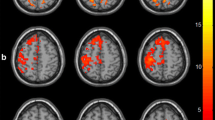

Alterations in the average strength of interhemispheric and intrahemispheric connectivity were investigated using stratified analysis according to stroke type and initial severity (Fig. 3; Table 5). Overall and homotopic interhemispheric connectivity at 2 weeks post-stroke was significantly disrupted compared to healthy controls regardless of stroke type and initial severity. However, ipsilesional and contralesional intrahemispheric connectivity did not show any significant differences compared to healthy controls. During the recovery period, changes in interhemispheric connectivity were more distinct than those in intrahemispheric connectivity. Global connectivity showed different alterations according to stroke type and initial severity. There were significant differences of alterations in overall and homotopic interhemispheric connectivity according to stroke type (type × time; overall, F = 4.34, p = 0.0404; homotopic, F = 8.59, p = 0.0044). Interhemispheric connectivity was significantly increased in the Hemorrhagic group (overall, t = − 3.56, p = 0.0018; homotopic, t = − 3.57, p = 0.0018) compared to the Ischemic group. There was no difference between groups according to severity. However, overall interhemispheric connectivity was significantly increased in the Mild and Moderate group (t = − 3.25, p = 0.0036). In contrast to interhemispheric connectivity, ipsilesional and contralesional intrahemispheric connectivity did not exhibit significant differences between groups or within groups. However, contralesional connectivity had a tendency to increase in the Mild & Moderate group and to decrease in the Severe group although differences in contralesional connectivity changes were not significant according to severity (severity × time, F = 2.99, p = 0.0876).

Altered interhemispheric and intrahemispheric connectivity in the motor network. a The strength of overall interhemispheric connectivity. b The strength of interhemispheric connectivity between homotopic regions. c The strength of ipsilesional intrahemispheric connectivity. d The strength of contralesional intrahemispheric connectivity. Error bars represent standard deviation (*p < 0.05; **p < 0.01; ***p < 0.001)